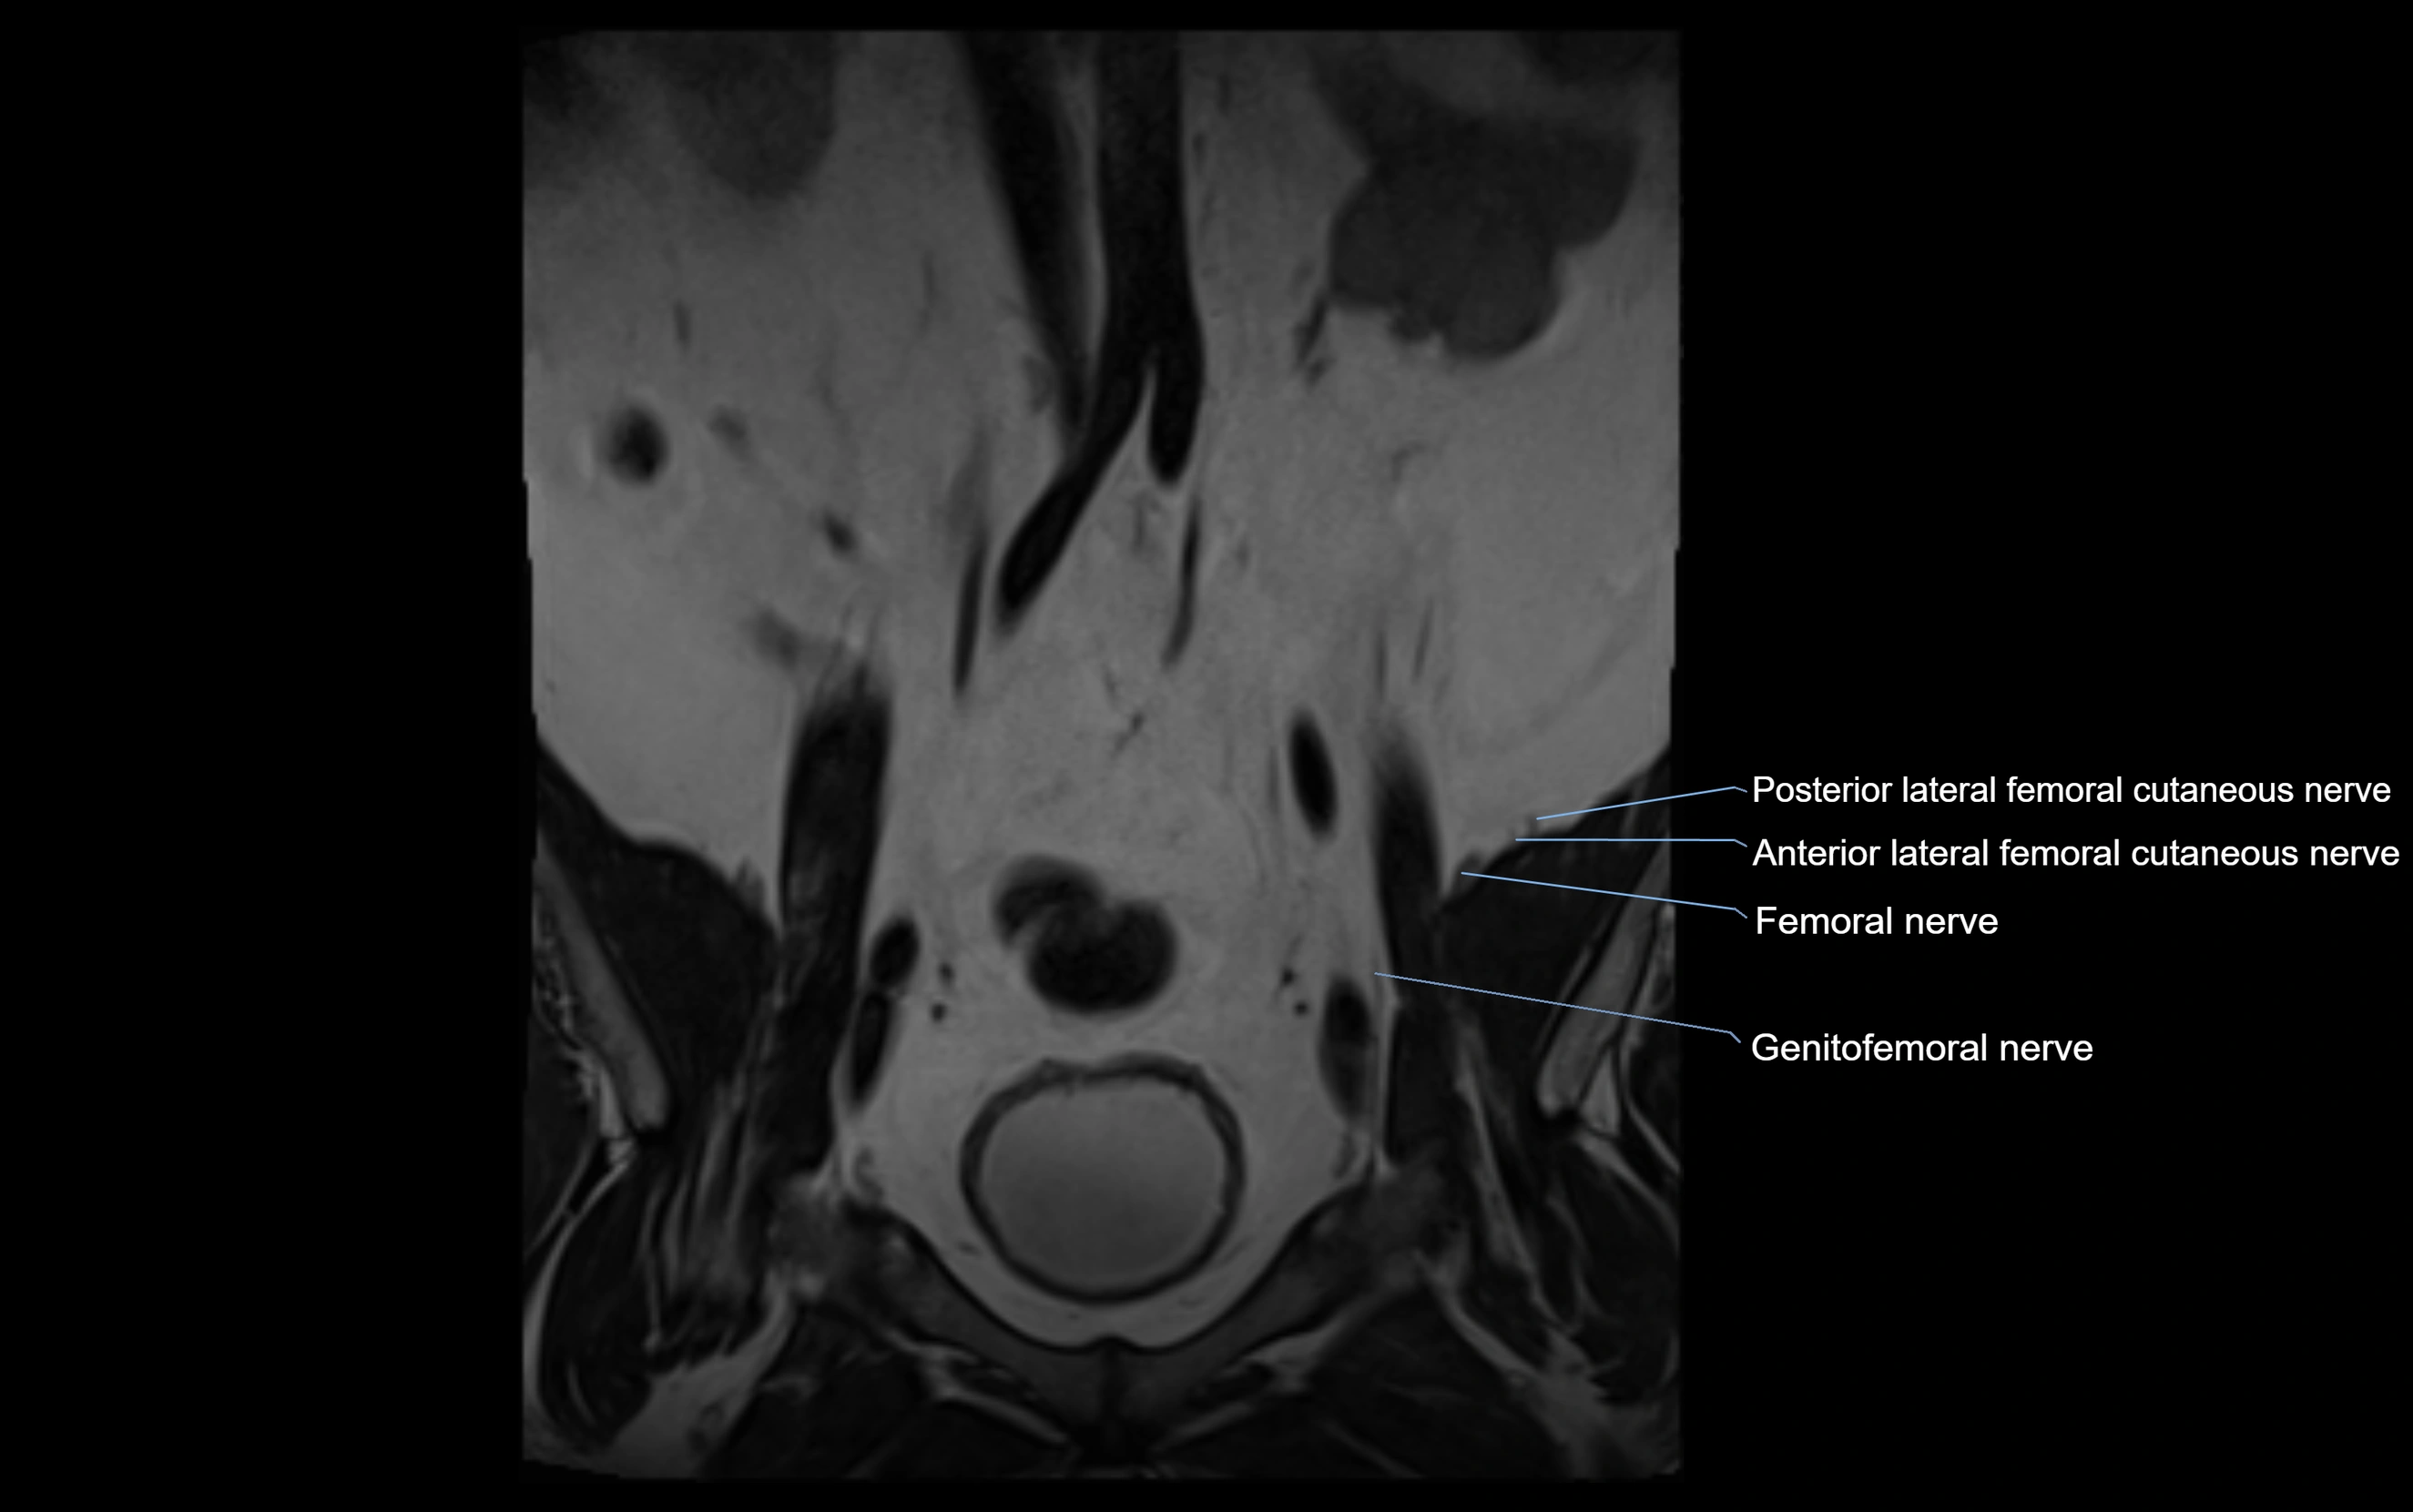

MRI Appearance

T1-weighted images:

• Nerve appears as a very thin low-to-intermediate signal intensity structure

• Surrounded by bright fat, aiding visualization

T2-weighted images:

• Nerve shows intermediate to mildly hyperintense signal compared to muscle

• Pathological involvement appears brighter

STIR (Short Tau Inversion Recovery):

• Normal nerve appears dark

• Inflamed or entrapped nerve appears bright hyperintense

T1 Fat-Sat Post-Contrast:

• Normal nerve enhances minimally

• Pathologic nerve (neuritis, entrapment, tumor infiltration) shows focal or diffuse enhancement

3D T2 SPACE / CISS:

• Nerve appears intermediate to mildly hyperintense compared to muscle

• Surrounded by bright fat or CSF, improving visualization

• Best sequence for mapping small pelvic nerves such as the anococcygeal

MRI image

image